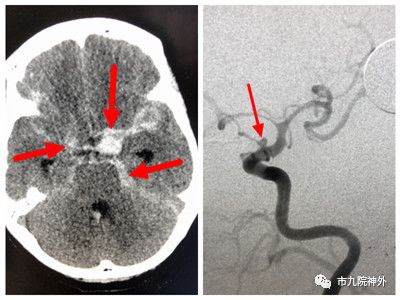

左图:术前CT见蛛网膜下腔出血;右图:DSA中箭头所示为血泡样动脉瘤